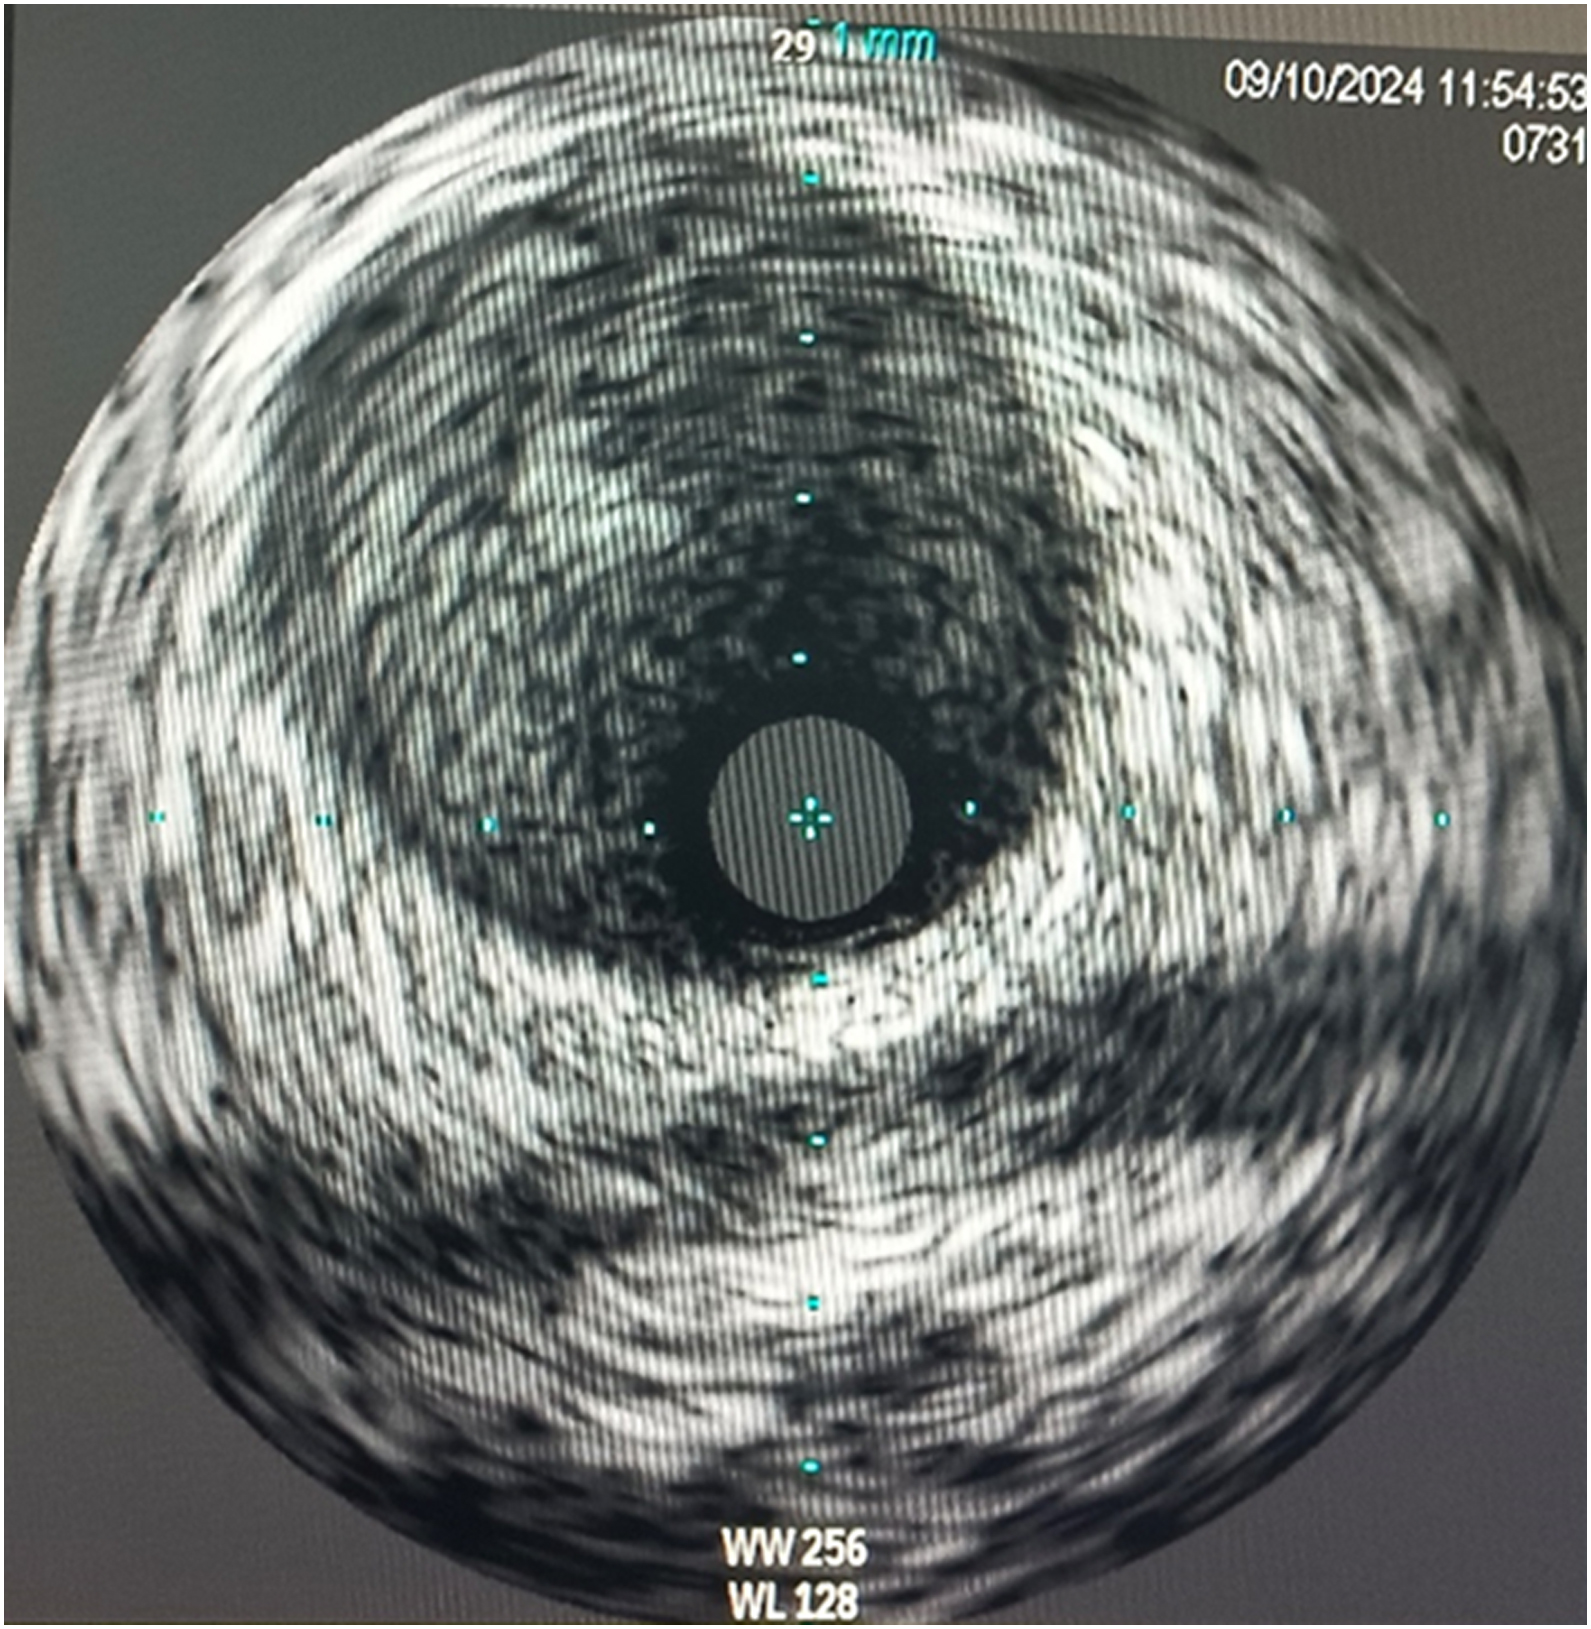

Inserted Sion wire and thrombuster to LAD revealed multiple red clots.SC balloon 2.0 x 15 mm, then 2.5 x 15 mm, was inflated at mLAD up to 12 atm. IVUS insertion to LAD revealed vessels¡¯ size LM 5-5.5 mm, pLAD 4-4.5 mm, mLAD 3-3.5 mm with intraluminal thrombus, dLAD 2.75-3 mm. Multiple inflations were done at mLAD with SC balloon 2.5 x 15 mm. After multiple SC balloon inflations, the CAG revealed slow flow phenomenon. Then, the operator performed thrombus aspiration, multiple SC balloon 2.0 x 15 mm inflation and gave IC integrillin 3.4 ml. The final angiogram was acceptable result. The anticoagulant was given after CAG. Chest pain was subsided and hemodynamic parameters remained stable. EKG recorded after angiography showed resolution of ST elevation at V1-3. Later, the patient was discharged with warfarin. The Aortomitral intervalvular fibrosa repair surgery was planned due to embolic complication.

5. Intravascular imaging is beneficial in determinating the mechanism of CAD, informing therapeutic strategy and confirming effective treatment of PCI.